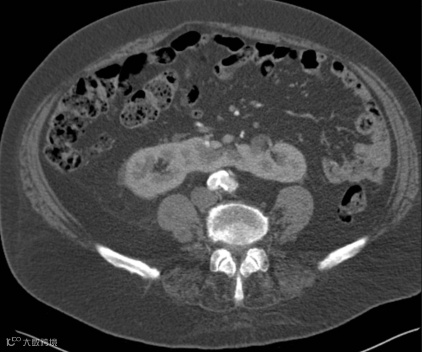

男,55岁,马蹄肾合并双肾多发结石,右肾积水(泌尿系气泡为导尿术后改变)。